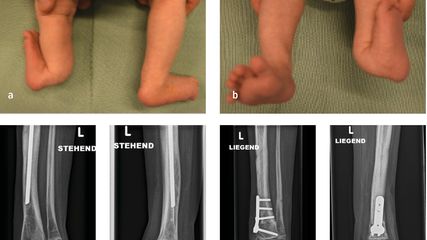

Der kongenitale Femurdefekt ist eine der spannendsten und komplexesten angeborenen Fehlbildungen in der Kinderorthopädie und in der klinischen Präsentation sehr vielgestaltig. Während auf den ersten Blick die Verkürzung des Beins/des Femurs augenscheinlich ist, sind es die assoziierten Veränderungen an Hüfte und Kniegelenk, welche die Therapie herausfordernd machen und vor einer Verlängerung adressiert werden müssen.

Zu den angeborenen Längsdefekten der unteren Extremität zählen neben dem kongenitalen Femurdefekt (CFD) die Fibulahemimelie (FH) und die Tibiaaplasie/-hemimelie. Der Femurdefekt reicht von einer milden Verkürzung des Femurs bis zu seinem fast vollständigen Fehlen, und auch die Fibulahemimelie kann sich von einer milden Verkürzung des Unterschenkels bis zu einer massiven Verkürzung mit schweren Veränderungen am Sprunggelenk präsentieren. Der CFD und die FH kommen fast immer gemeinsam vor, wobei die meisten Fälle eine klare Dominanz der einen oder anderen Pathologie zeigen und die sekundäre Deformität sich oft nur durch minimale Veränderungen an Knochen oder Gelenk präsentiert. Die Tibiaaplasie/-hemimelie ist oft mit Syndromen mit zusätzlichen Fehlbildungen oder Duplikaturen an Hand und Fuß verbunden. Diese Form ist mit einer Inzidenz von 1:1000000 sehr selten.

Milde Formen – Typ 1A – zeigen oft nur einen leichten Schenkelhalsvarus und eine verminderte femorale Antetorsion beziehungsweise Retroversion zusätzlich zur Verkürzung. Oft zeigt sich bei diesem Typ auch eine milde subtrochantäre Varusstellung und Sklerose. Mit zunehmendem Schweregrad addiert sich eine azetabuläre Dysplasie, wobei besonders die obere und hintere Überdachung der Hüfte vermindert ist. Beim Typ 1A ist in seltenen Fällen keine vorbereitende Operation erforderlich, insbesondere wenn die Überdachung der Hüfte sehr gut ist und ein CE-Winkel von über 20 Grad vorliegt. Es kann dann direkt mit einer Verlängerung des Femurs begonnen werden. Je nach verwendeter OP-Technik können eine eventuell vorhandene Retroversion und Varusstellung im Rahmen der Verlängerungsoperation akut über eine zusätzliche proximale Osteotomie und Montage an den oberen Teil des Fixateurs adressiert werden. (Abb.1).

Abb. 1: Operative Versorgung eines CFD rechts mit Varusstellung an der Hüfte und subtrochantärer Sklerosierung